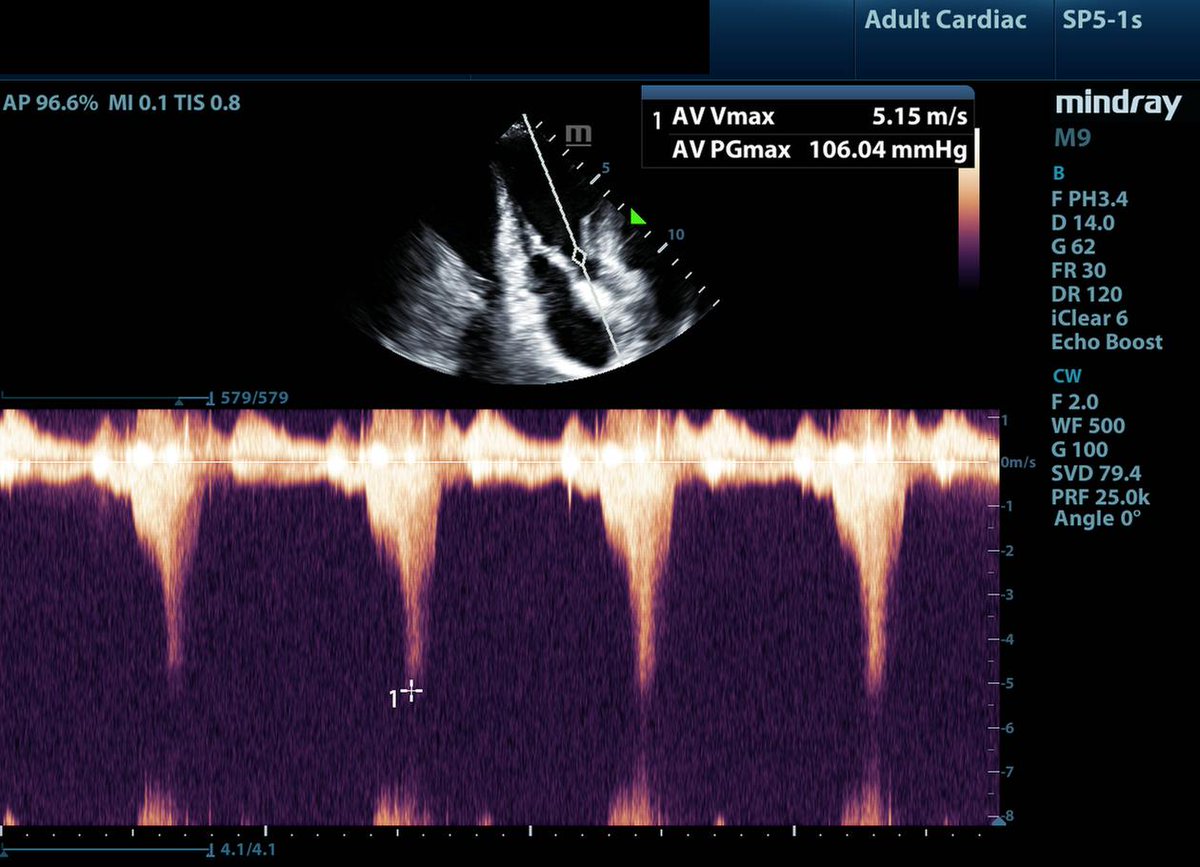

2/10: When you see a pt. who is "persistently hypovolemic" that transiently responds to fluid loading. First, ensure not bleeding.🩸 Second, instead of assuming they are just really dry, think about dynamic LVOTo, intracavitary gradients, or diastolic dysfunction. Giving them 15L of fluid to treat persistent fluid responsiveness is likely not the right move.